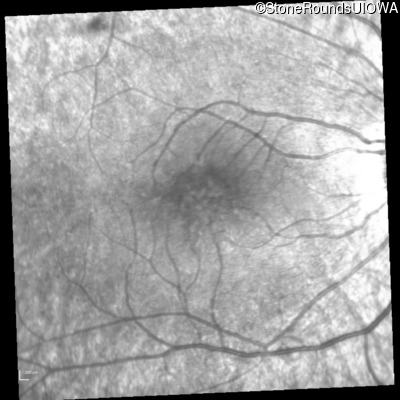

Infrared Fundus Photograph - Right - 20/32 -1

Exemplar